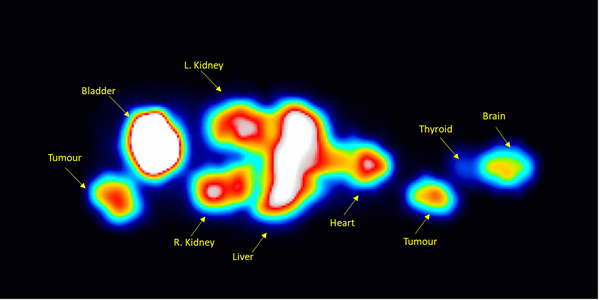

Mouse phantom filled with Tb-161 imaged with General Purpose collimator. Image Credit: Scintica Instrumentation Inc.